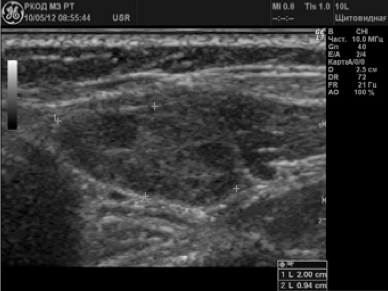

В 58 (38,2%) случаях было заподозрено метастатическое поражение лимфатических узлов. Измененные ЛУ имели размеры от 6 до 65 мм; 72,4% лимфатических узлов имели шарообразную форму, П/ПЗ2,0; 17,3% — неправильную форму в виде конгломератов. У 24 (41,4%) пациентов были выявлены единичные измененные лимфоузлы; у 34 (58,6%) — множественные. У 79,3% лимфоузлов отсутствовала дифференциация на кору и ворота; у 20,7% — ворота определялись в виде мелкого гиперэхогенного включения. 70,8% лимфатических узлов были гипоэхогенными (рис. 3); 12% — анэхогенными; 17,2% — неоднородную структуру с участками повышенной и пониженной эхогенности, с жидкостными включениями и кальцинатами (рис. 4).

Рисунок 4.

Метастатаз солидно-жидкостного строения в лимфоузле шеи